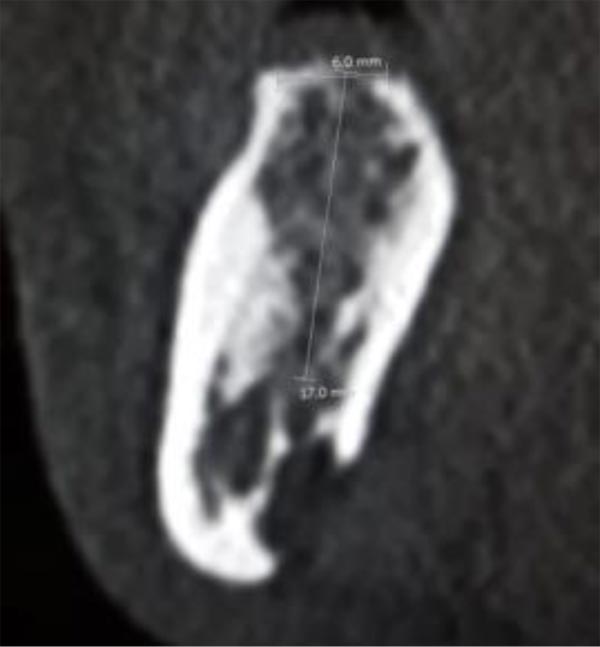

In this radiographic exam, we found an oval notch with radiolucent, clear and regular borders, located in the inferior portion of the horizontal branch of the mandible, on the lingual side, near the angle of the mandible, and below the mandibular canal. The X-ray allowed precise measurement showing a height ranging between 13.5 mm and 17 mm and breadth between 6 and 8 mm (Figs. 4-5).